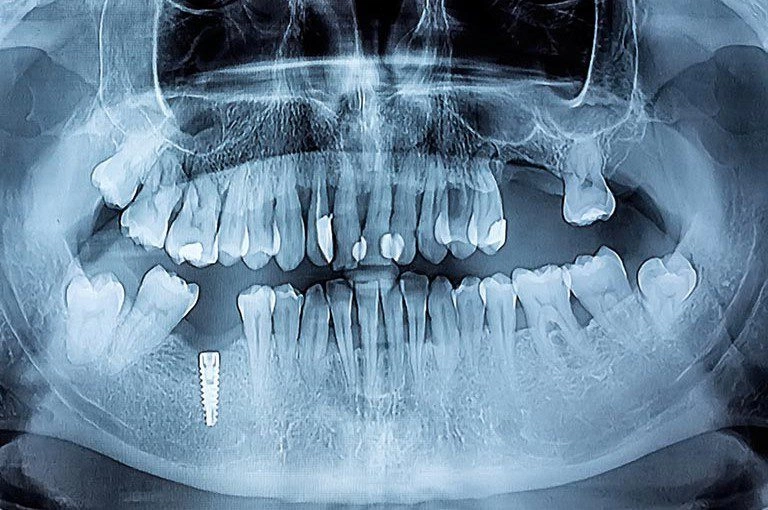

Un implante inteligente es, en esencia, un implante dental convencional al que se le integran microtecnologías capaces de recoger información sobre tus dientes. Estos sistemas pueden incluir sensores que registran variables como:

- Presión o carga masticatoria

- Temperatura local

- Cambios en el pH: Variaciones en el nivel de acidez en los tejidos y fluidos de la boca en esa zona concreta

- Señales relacionadas con inflamación o infección

El objetivo es detectar de forma precoz cualquier problema y facilitar un seguimiento más preciso del tratamiento.

Los implantes tradicionales tienen tasas de éxito muy elevadas, pero no están exentos de complicaciones. Una de las más relevantes es la periimplantitis, una inflamación de los tejidos que rodean el implante y que pueden comprometer su estabilidad.

La incorporación de sensores en implantes dentales es un campo activo de investigación dentro de la odontología digital y la bioingeniería, aunque esta evolución en el mundo de la tecnología en implantes dentales, no se limita a los sensores. Sino que también incluye:

- Planificación digital en 3D

- Cirugía guiada por ordenador

- Materiales biocompatibles avanzados

- Sistemas de carga inmediata más seguros